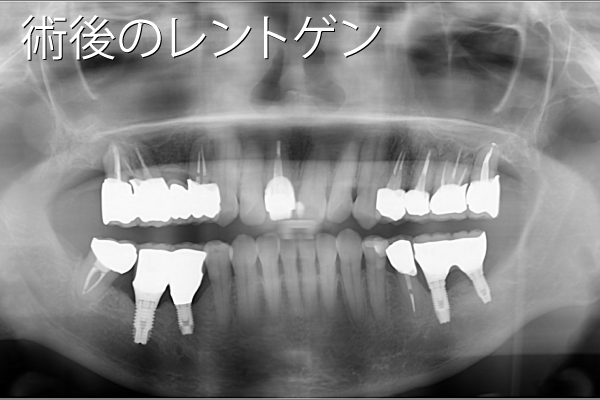

- 性別年齢

- 男性:50歳

- 治療内容

- 下顎の奥歯にインプラント3本

- 金額

- 132万円(税込)

- 来院理由

- 歯周病が進行してきたため、噛めなくなってきた。インプラントを含めて総合的にきちんとした専門医の治療を受けたい。

- 施術の

副作用

(リスク) - 経過とともになくなりますが、術直後に腫れや違和感を感じることがあります。